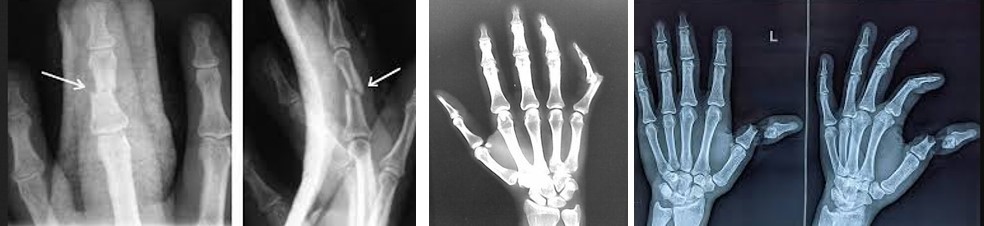

Для виключення переломів фаланг пальців та відриву кісткового фрагменту разом з сухожилком, застосовують рентгенографію у двох проекціях. Чому саме рентгенографія є першим методом діагностики?

Переломи кісток кисті – поширена травма. На частку переломів кісток кисті припадає близько 35% всіх травматичних пошкоджень кісткової системи. Зазвичай причиною перелому кісток кисті стає удар по кисті або падіння з упором на кисть, також причиною є виробничі травми – попадання пальців чи кисті в промислові агрегати. Переломи кісток кисті включають переломи зап’ястя, п’ясткових кісток та фаланг пальців. (с)

Застаріла травма сухожилка розгинача пальця на рівні дистальної фаланги. Результат консервативного лікування